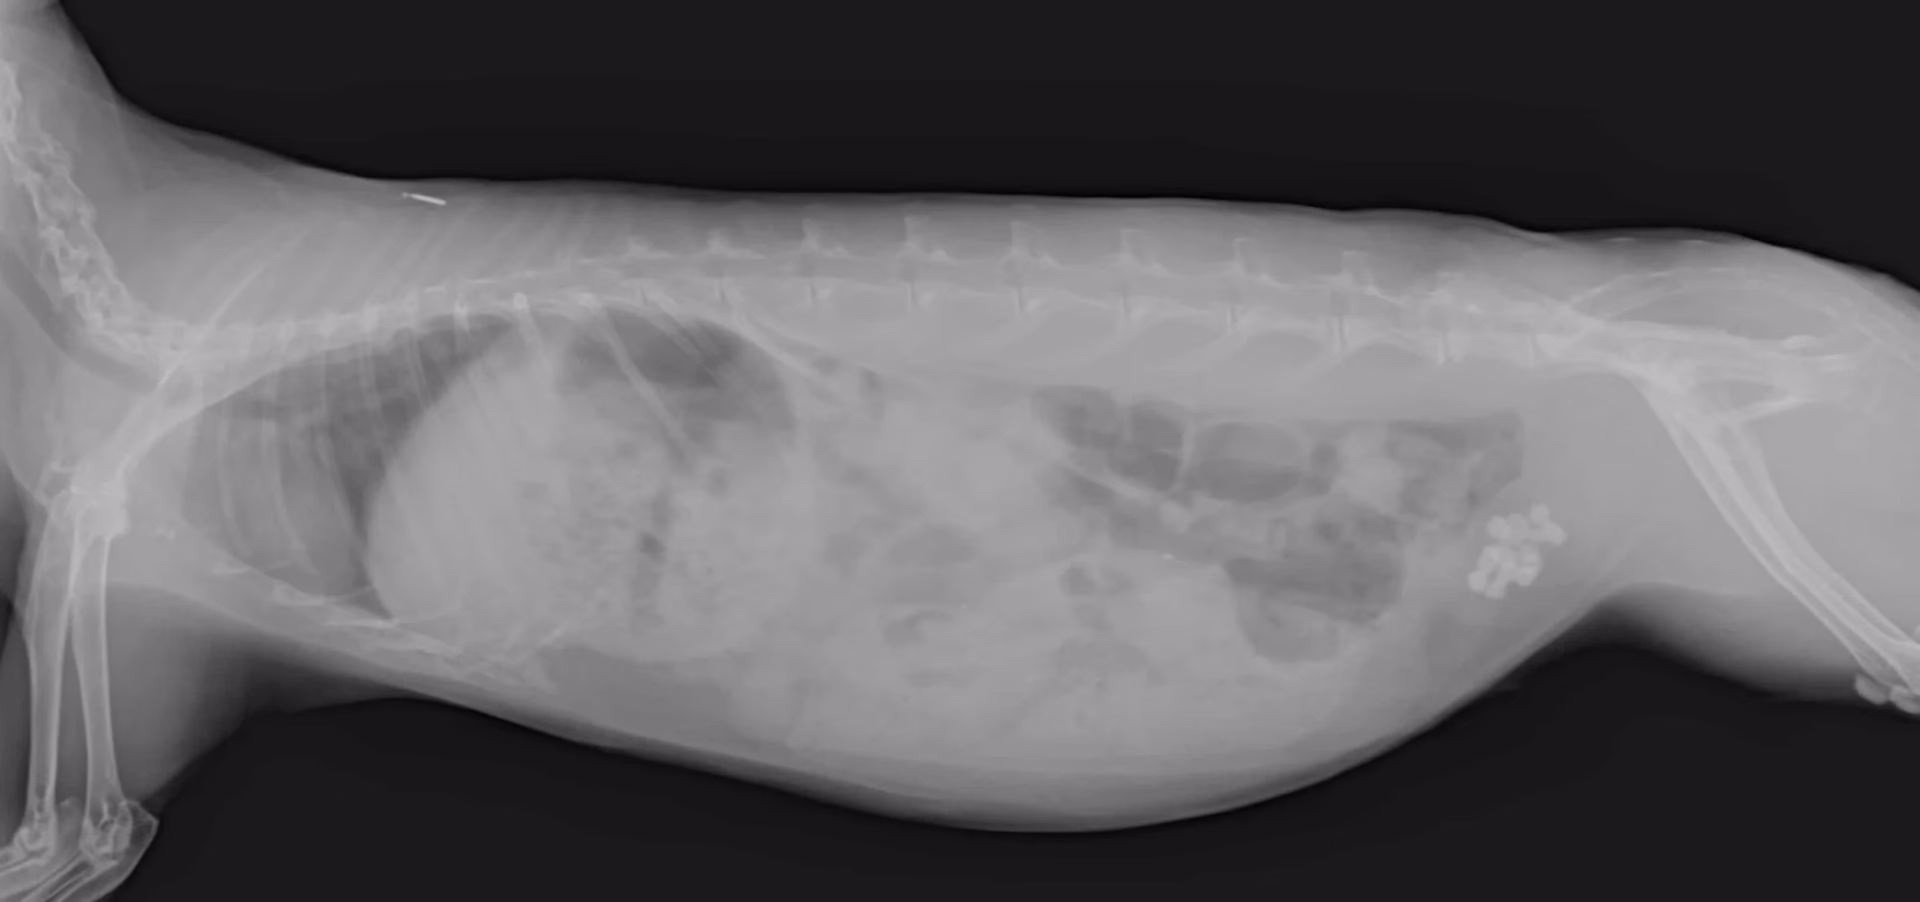

Las pruebas de imagen son herramientas diagnósticas cruciales. Las radiografías (rayos X) suelen ser muy efectivas para visualizar cálculos de calcio, ya que son radiopacos (se ven blancos en la imagen). La ecografía (ultrasonido) también es útil para evaluar la vejiga, detectar barro que quizás no se vea bien en la radiografía, y examinar los riñones.